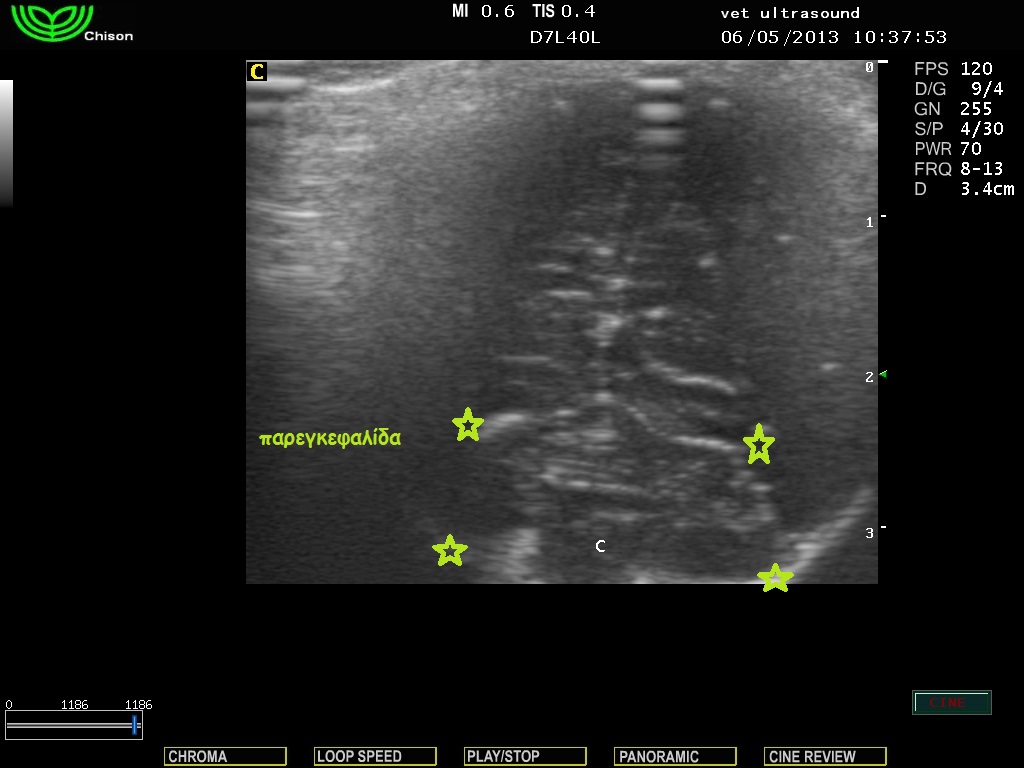

Εγκάρσια τομή με φορά της δέσμης του υπερήχου προς το ινιακό τρήμα.